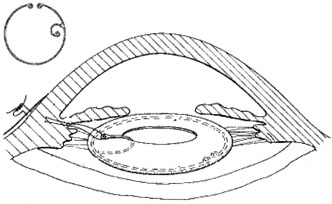

A mature cataract precludes visualization of the fundus. A B-scan ultrasonographic examination provides a real-time, two-dimensional (2D), cross-sectional image of the globe along the marked axis of the probe (Fig. 3). Cataracts are more common in patients with chronic retinal detachment, prior trauma, or intraocular tumors; therefore, a B-scan study is helpful in excluding structural posterior segment pathology before surgery on a mature cataract. Although a negative result to B-scan evaluation is reassuring, the surgeon should remember that it does not predict postoperative visual outcome. The B-scan can be thought of as a picture of Cincinnati from an airplane; the office buildings may all be standing, but you cannot tell whether the people in them are working.